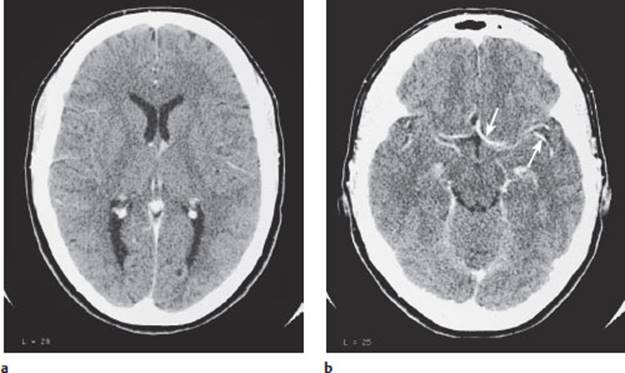

Fig. 4.3 Normal CT scan of the head. a Note the symmetrical, normal-sized frontal and occipital horns of the lateral ventricles. The cerebral cortex and deep white matter can be distinguished from each other, and the falx cerebri can be seen in both the frontal and occipital regions. A number of blood vessels can be seen. Also note the bilateral calcifications of the choroid plexus of the lateral ventricles. b Some of the blood vessels around the base of the brain (arrows) are well seen after the administration of contrast medium.